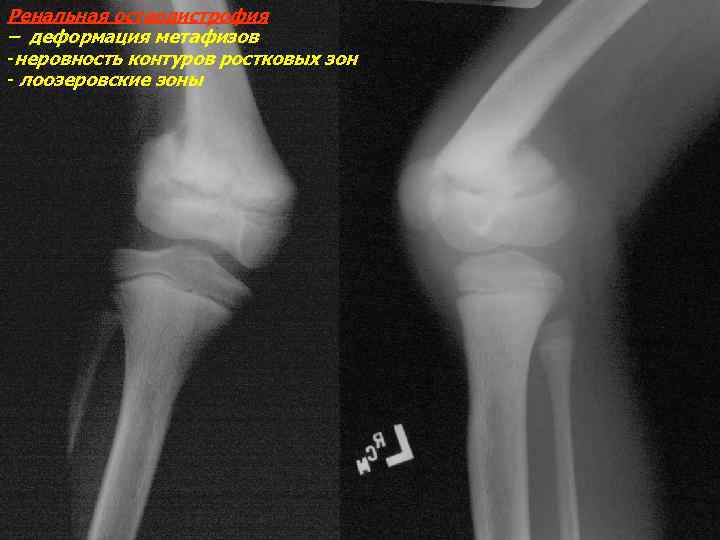

Рентгеновские снимки и визуализация болезни Педжета

Раздел: Мудрость в объективе